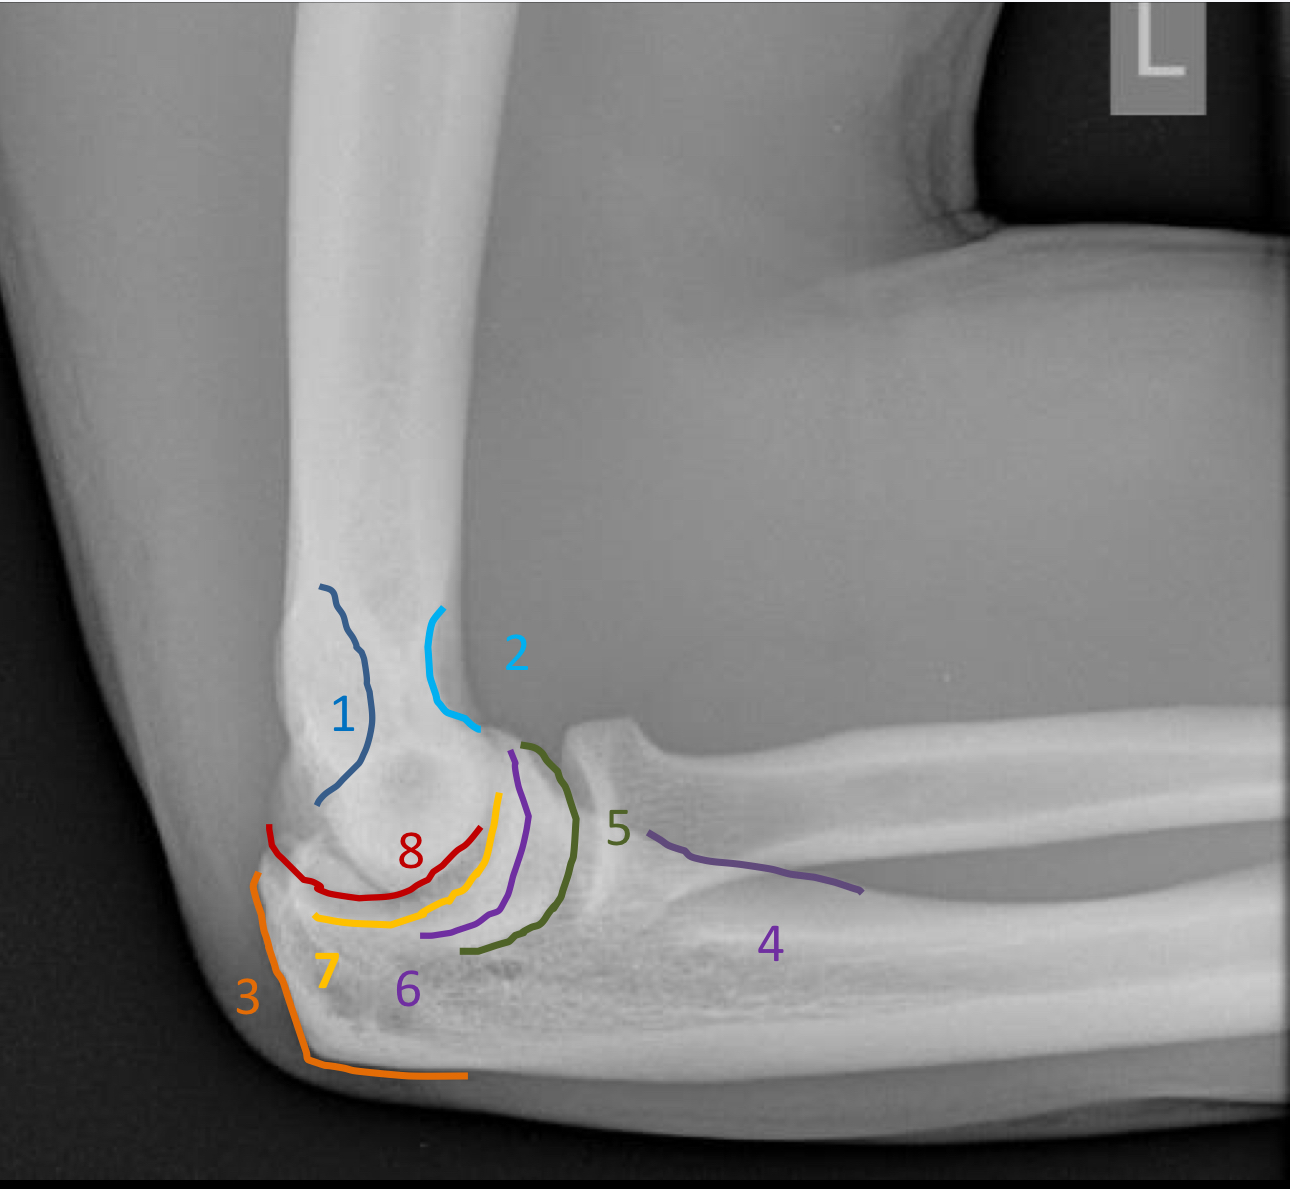

1?

lateral supracondylar ridge

2?

olecranon process

3?

coronoid process

4?

radial tuberosity

5?

radial notch of the ulna